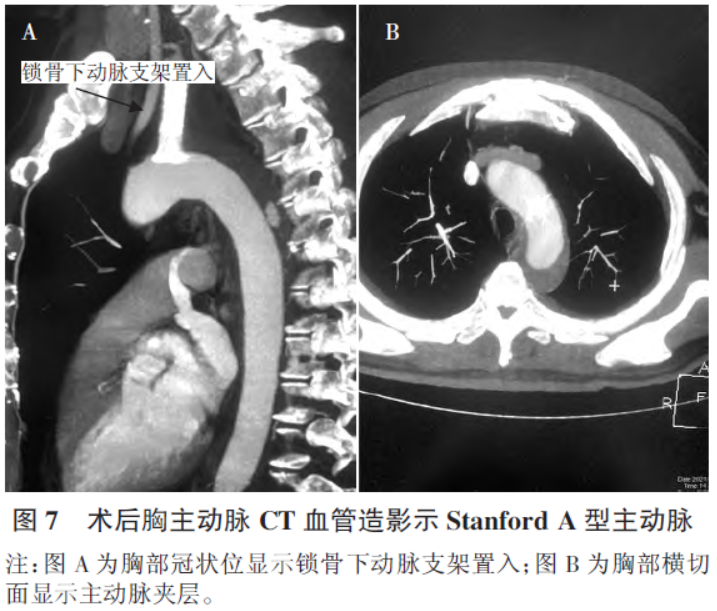

术后第2天胸部增强CT证实主动脉夹层(主动脉弓及降主动脉)为Stanford A型,见图7。术后第8 天再次行胸部增强CT 复查提示主动脉弓、降主动脉壁间血肿并少量出血。2022年6 月患者再次复查行造影检查,主动脉造影,主动脉夹层未显影,左锁骨下动脉起始部无造影剂外渗,如图8。